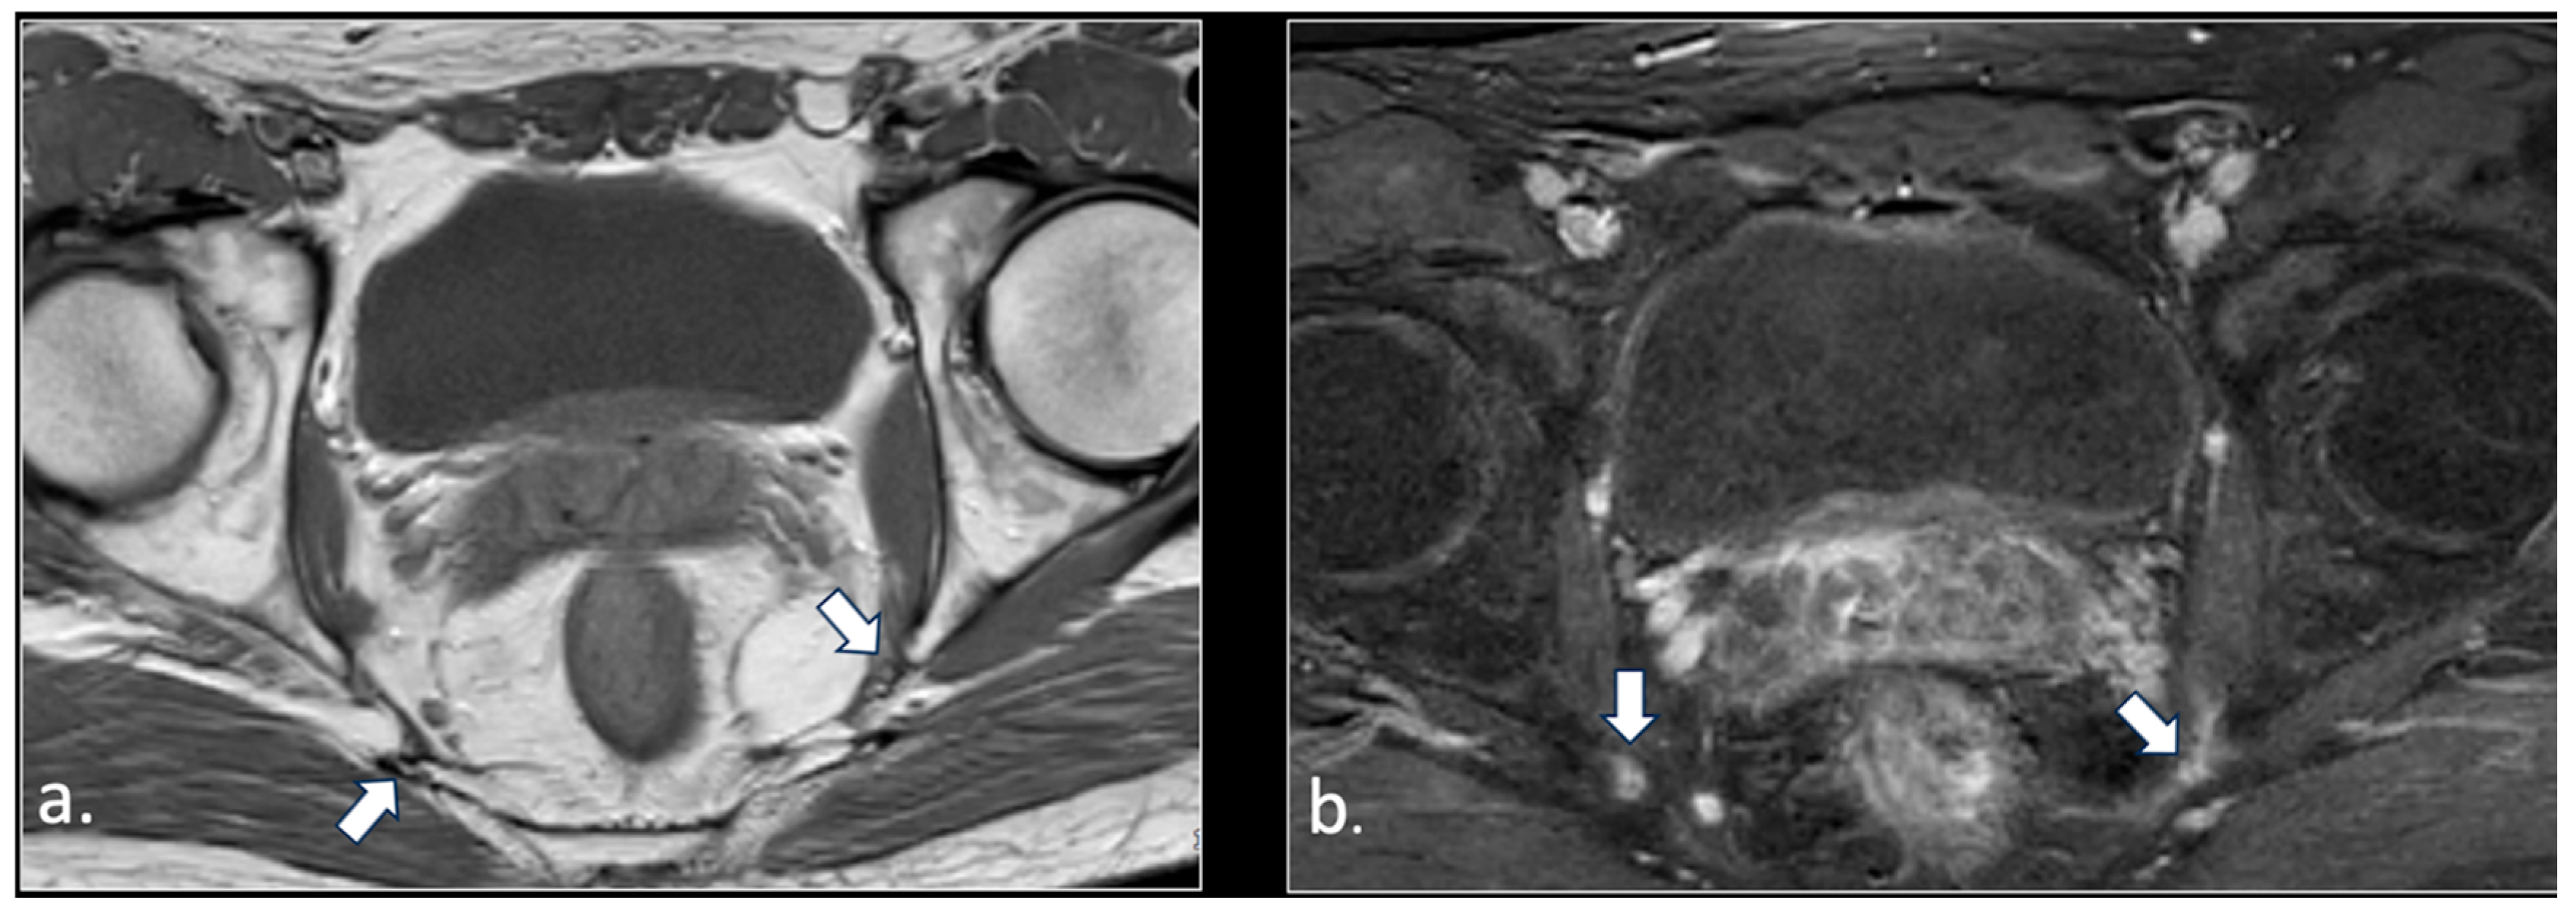

- Unilateral rupture of puborectal and/or pubococcygeal muscle (4 patients);

- Perineal fibrosis involving Alcok’s canal (4 patients);